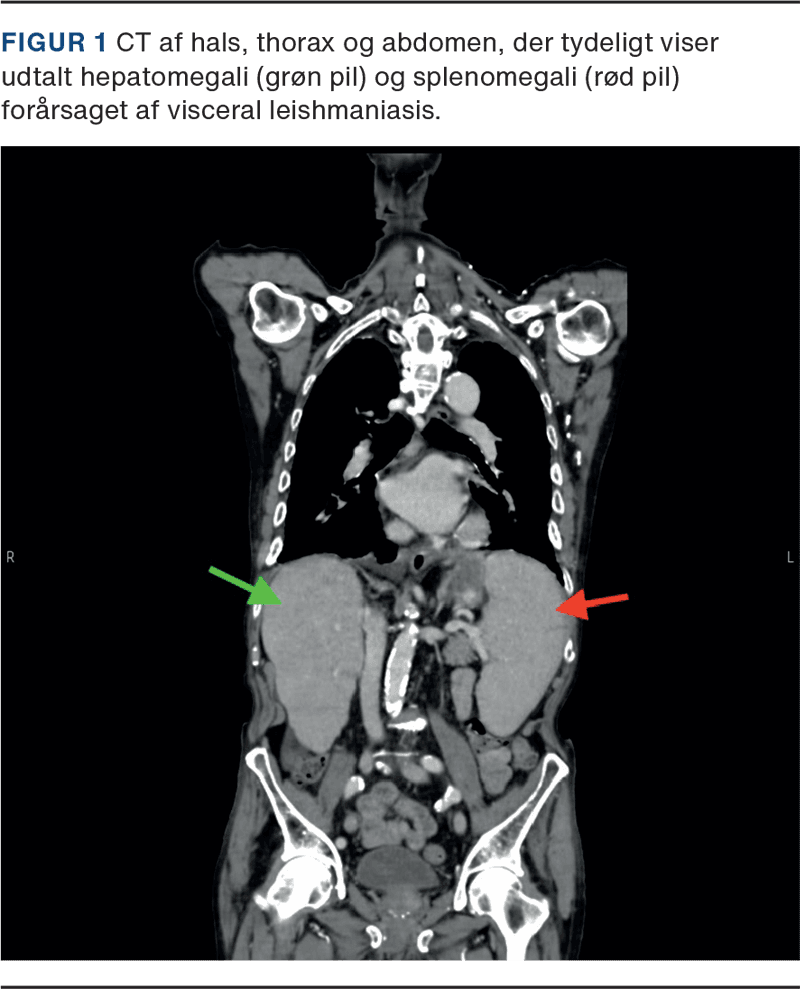

En 86-årig etnisk dansk mand diagnosticeret med letkæde lambda myelomatose i 2. linjebehandling med kemoterapi blev fulgt i hæmatologisk regi siden 2019. I løbet af et år havde patienten ca. ti indlæggelser med nedsat almen tilstand, recidiverende feber og forhøjede infektionsparametre uden fokus. Patienten opnåede kun kortvarig lindring på intravenøs antibiotisk behandling førend næste indlæggelse. En CT under en af indlæggelserne viste både hepato- og splenomegali (Figur 1). Blodprøver viste pancytopeni med hæmoglobin < 7,0 mmol/l, leukocytter < 2,0 mia./l og trombocytter < 60 mia./l, som initialt blev tilskrevet enten nytilkommet myelodysplastisk syndrom (MDS) eller progressiv myelomatose.

Grundet langvarig uafklaret feber blev der udbedt tilsyn fra infektionsmedicinsk afdeling. Ekspositioner viste en ekstensiv rejsehistorik i både Asien, Sydamerika og Sydspanien. Der anbefaledes supplerende mikrobiom 16S/18S på ethylendiamintetraacetat (EDTA)-blod. Denne var positiv for Leishmania. Sekvensering af internal transcribed spacer (ITS)-genet identificerede L. donovani/infantum-komplekset, hvilket bekræftede diagnosen visceral leishmaniasis. Dette forklarede patientens hepato- og splenomegali samt pancytopeni. Den seneste knoglemarvsbiopsi blev reevalueret af patologerne, men uden fund af amastigoter, som kan ses ved leishmaniasis. Patienten opstartede intravenøs liposomal amphotericin B og mærkede klar bedring allerede efter første behandling. Kort efter anden dosis ophørte feberen, og patientens biokemi bedredes. Hæmatologisk set var myelomatosen under kontrol, og patienten blev sat i behandlingsfri observation efter udtrapning af steroid.